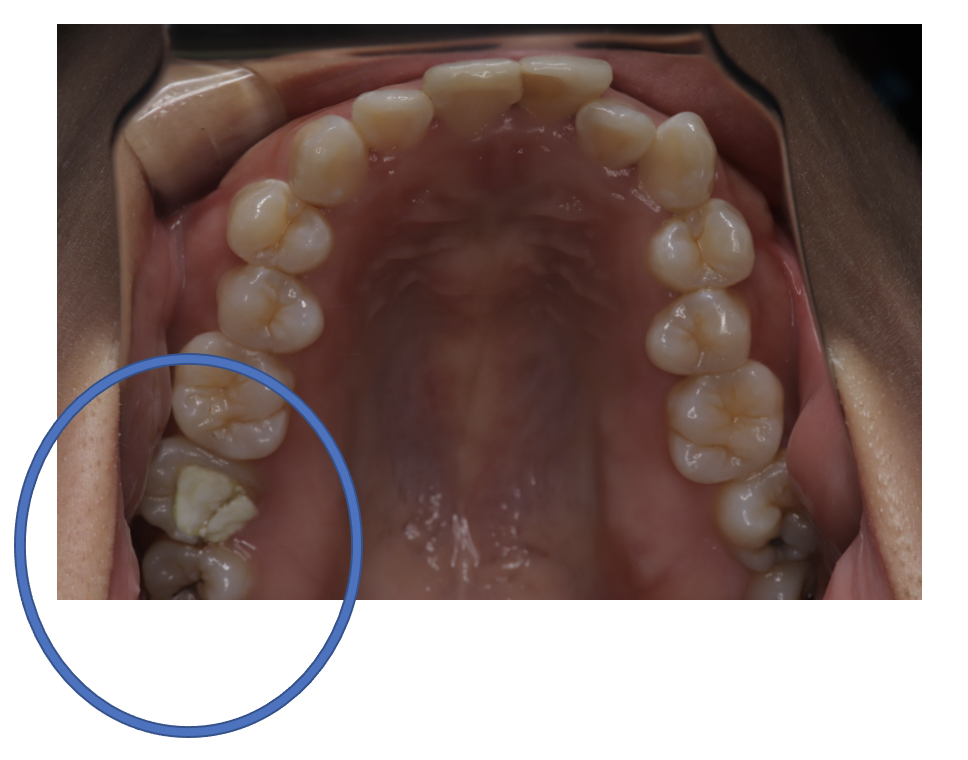

Before

| 備考 | 院長より 親知らずが原因で、親知らずの一個手前の歯に磨けない場所ができてしまい、残念ながら神経まで達する重度の虫歯になってしまいました。 フルジルコニアCrで被せて機能を回復しています。一番奥の親知らずが存在していては、手入れが難しく、再び手前の歯に虫歯、歯周病のリスクを高める存在になっていたので、相談の上、抜歯することになりました。 |